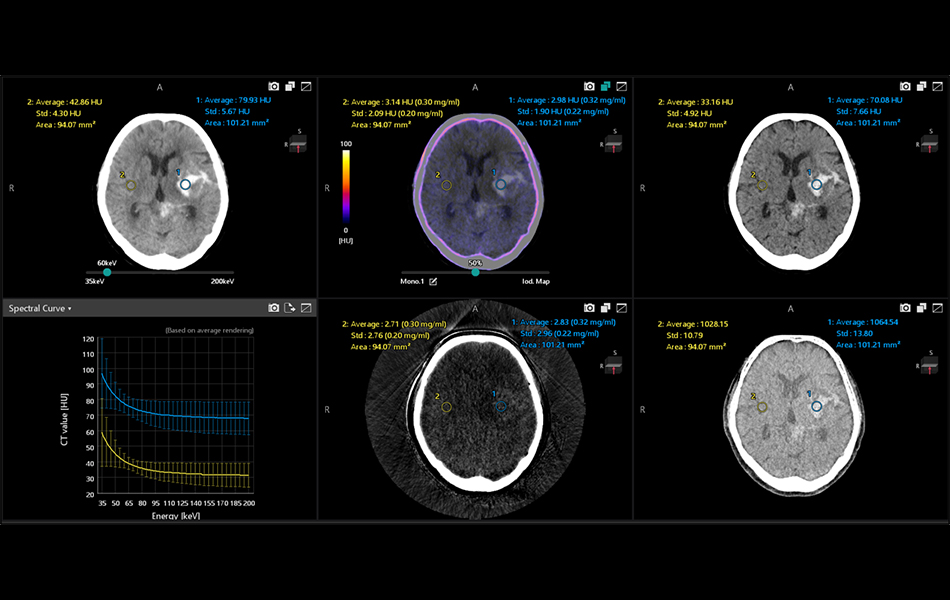

Spectral Cardiac Analysis (7.15.6)

Allows the user to review ECG gated spectral cardiac imaging to visualize and quantify iodine distribution, assess electron density and effectiveZ values within the myocardium and coronary arteries. Extraction of the myocardium and coronary arteries are supported by Vitrea’s industry leading myocardium (Myocardial Perfusion) and coronary artery analysis (Cardiac Analysis) applications. Spectral Analysis can inherit these extraction results.

Spectral Vessel Analysis (7.15.6)

The ability to display CPR (curved plane reformat), SPR (stretched curved plane reformat) and crosscut to review coronary artery spectral image.

Spectral Brain Analysis (7.15.6)

Spectral iodine maps are designed to assist a physician in visualizing iodine concentration and distribution in the brain.